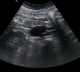

Ruptured lymphangioma

Lymphangiomas are malformations of the lymphatic system characterized by lesions that are thin-walled cysts; these cysts can be macroscopic, as in a cystic hygroma, or microscopic. The lymphatic system is the network of vessels responsible for returning to the venous system excess fluid from tissues as well as the lymph nodes that filter this fluid for signs of pathogens. [Source: Wikipedia ]